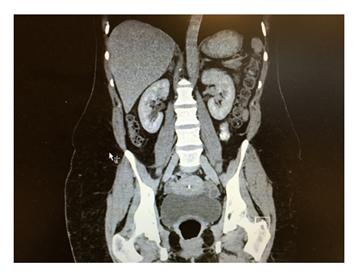

Her inflammatory markers were raised with C reactive protein (CRP) reading at 150 mg/L and White cell count of 10.2X 109. Erect chest X-ray showed large amount of air under the diaphragm and abdominal X-ray showed dilated small bowel loops (Figure 2) in the left upper quadrant and free air between the loops. The patient underwent emergency laparotomy with hissing of air escape at peritoneal opening. All organs were examined and no abnormality was seen. All four quadrants examined thoroughly but no evidence of any bowel leak found. There were no signs of any inflammation in pelvis and a negative laparotomy was concluded. The patient had uneventful recovery and was discharged home on 4th post-operative day. The patient underwent further abdominal and pelvic CT scan Figure 3-5 with contrast few days after the operation for completion of investigation and no abnormality was seen. The patient was reviewed in the clinic one and three months after the operation with no complaint and no post-operative complications.

Figure 4&5 Normal follow up CT scan.